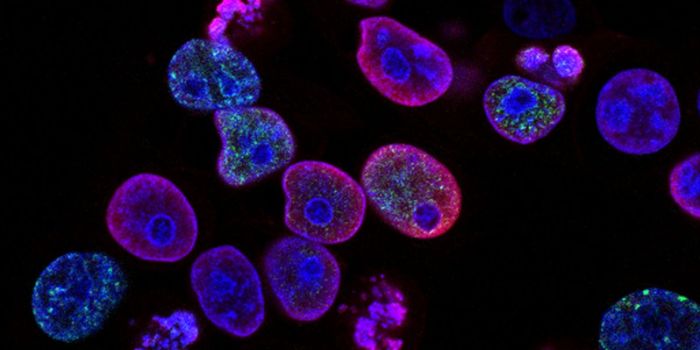

JUL 26, 2020Cannabis SciencesResearchers at the University of Newcastle have found that a modified version of medicinal cannabis can kill and inhibit ...

AUG 15, 2022CancerToday, August 15, marks the anniversary of the death of Abigail Adams Smith, the daughter of the second President of the ...